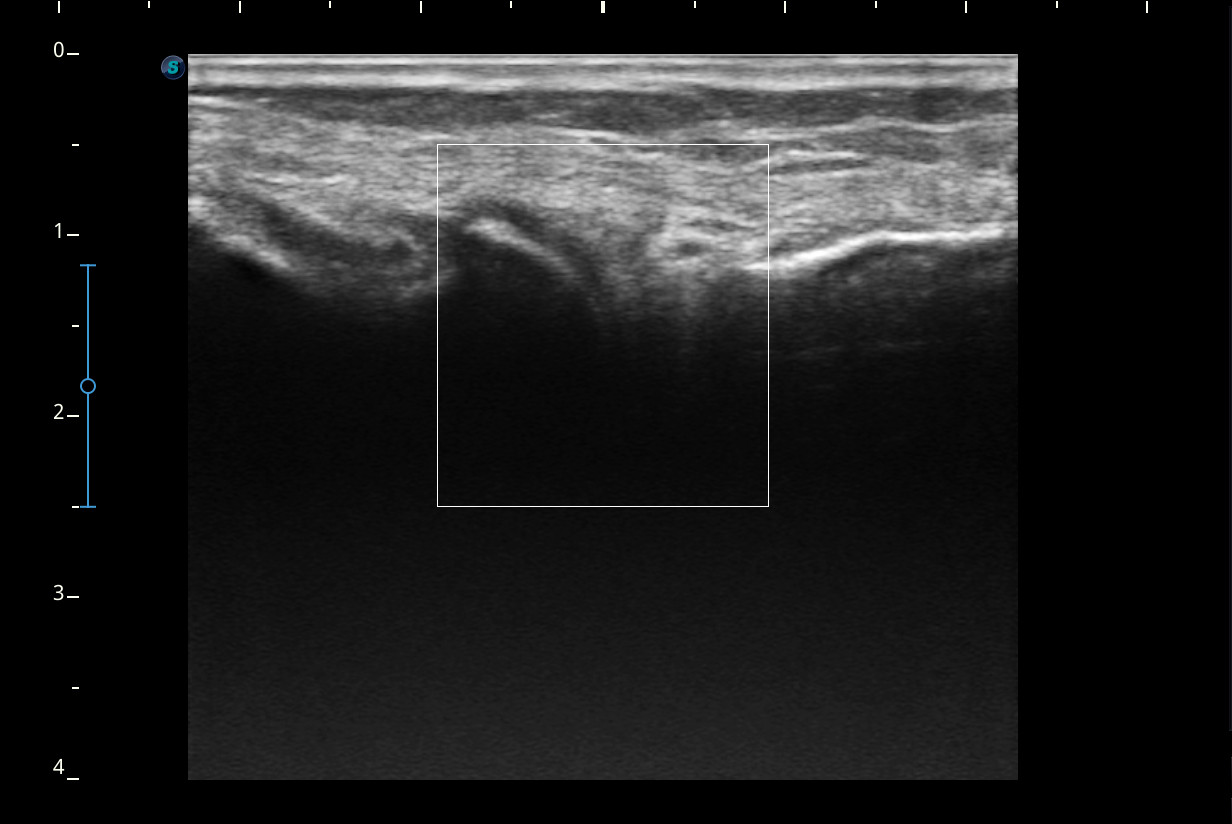

Rodilla sin derrame articular. No se aprecian lesiones en Ligamentos colaterales. Ligamento rotuliano sin hallazgos valorables. Rotura menisco interno y dudosa fisura menisco externo. Tendones rotuliano y cuadricipital normales.

Resonancia magnética confirma rotura cuerno posterior menisco interno.

Rotura cuerno posterior menisco interno.